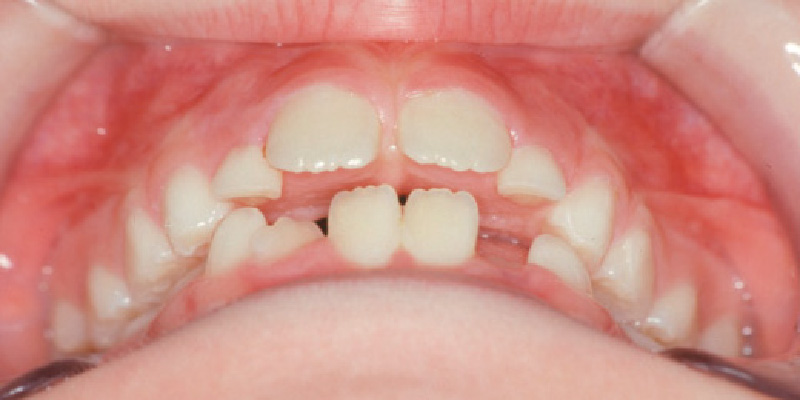

治療前

[7歳5か月]

【お顔】4歳頃に下顎を打撲しています。下顎は左にずれ、オトガイ(下顎の先端部分)が大きく左に位置しています。【口腔内】下顎の前歯の正中(真ん中)は左にずれています。上下前歯の前後的・垂直的なズレがあり、わずかな開咬の状態です。